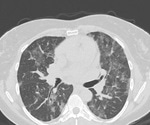

New virtual tool to help the world diagnose COVID-19 in the lungs

World's only online image-based tool to improve COVID-19 diagnosis launched

AI tool could accurately predict which COVID-19 patients will develop respiratory disease